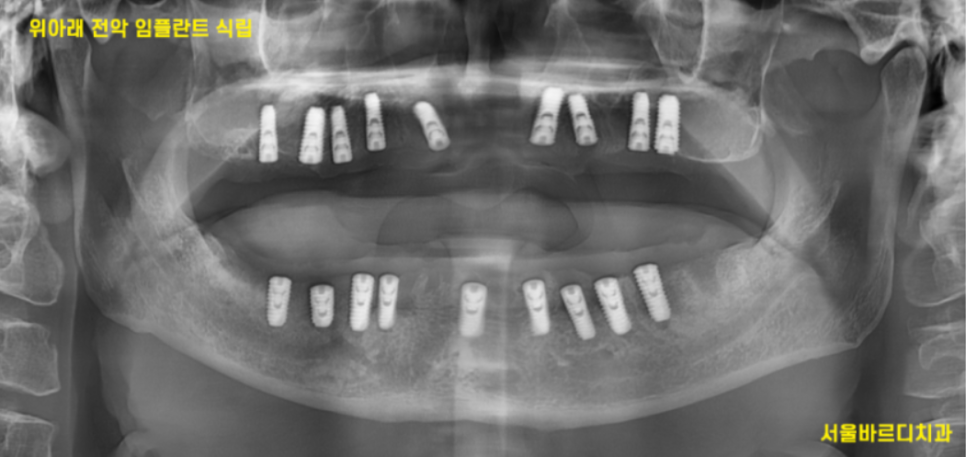

또한 임플란트 치료가 끝날 때까지

임시 틀니를 쓰셔야하는 전악 임플란트 환자분

앞니 임플란트 수술 환자분들은 2차 수술법으로 진행합니다.